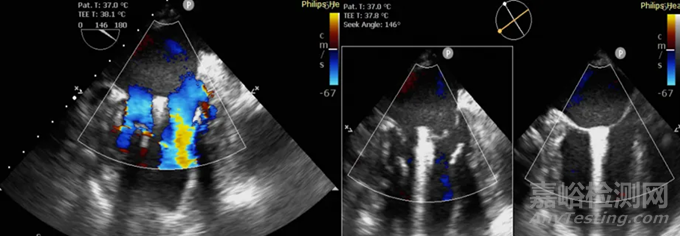

健世科技自主研發(fā)的經導管二尖瓣修復夾持系統(tǒng)JensClip為治療重度二尖瓣返流的患者而設計。其將二尖瓣瓣葉的小塊夾緊,瓣膜在夾子任一側繼續(xù)開合,允許血液在兩側流動,同時減少錯誤方向的血液流動。

▲JensClip®經導管介入瓣膜夾(緣對緣)修復系統(tǒng)超聲圖像,可以看見穩(wěn)定的瓣膜二孔化形成

Jens Clip由兩支夾持臂的夾子、可調彎導管及輸送系統(tǒng)組成。

夾持輸送系統(tǒng)透過可調彎導管提供的管道前進,以控制植入式夾子。兩支夾持臂可轉動并通過連續(xù)范圍設定在任何角度,防止拉伸過度導致瓣葉撕裂。在兩支夾持臂抓住及拉動瓣葉后,可由鎖定機制結構固定該器械。兩側夾臂在各個角度均能有效鎖定,避免過度牽拉瓣葉造成的損傷。導管的手柄控制器械的運用,讓夾子可分別移動。

在手術過程中,Jens Clip輸送系統(tǒng)的設計使醫(yī)生能360度全方位操控器械。Jens Clip使用帶有爪壁的鎖定機制,配有可多邊抓住瓣葉的簡單結構設計,便于使用,且靈活性更佳。